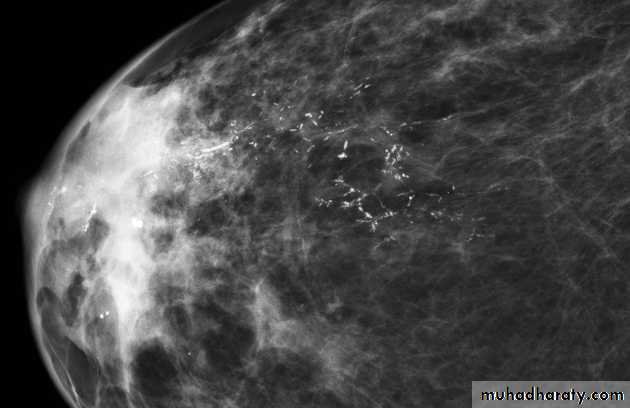

Micro calcifications

Micro calcifications are tiny specks of calcium in the breast. Micro calcifications seen on a mammogram are of more concern than macrocalcifications, but they do not always mean that cancer is present. The shape and layout of microcalcifications help the radiologist judge how likely it is that cancer is present.

mammogram

In most cases, the presence of microcalcifications does not mean a biopsy is needed. But if the microcalcifications have a suspicious look and pattern, a biopsy will be recommended. (During a biopsy, the doctor removes a small piece of the suspicious area to be looked at under a microscope. A biopsy is the only way to tell if cancer is really present.)